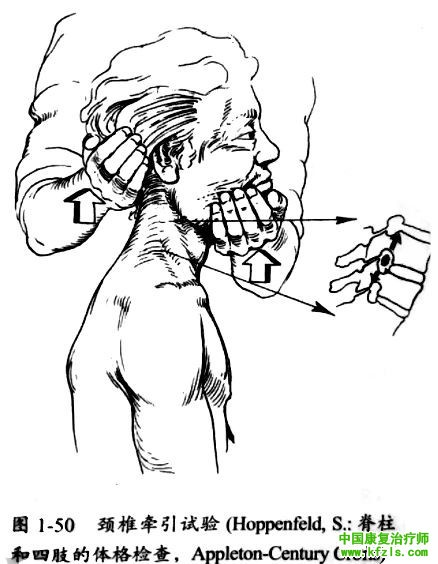

诱发或减轻骨关节炎症状的常规检査 >>颈椎牵引试验颈椎牵引试验阳性为牵引颈部向上可以缓解疼痛。牵引可缓解神经孔狭窄引起的疼痛,主要是因为扩大神经孔、降低小关节关节囊压力及缓解颈部肌肉痉挛。

检査方法:检査者一手托住患者颏下,另一手托住患者枕部,然后逐渐向上牵引头部(图1-50),如患者出现颈部和上肢的疼痛减轻,即为阳性。